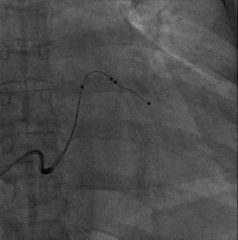

尝试抓捕器在右房抓捕runthough导丝成功,并进行牵拉

非常幸运,通过抓捕器的牵引力,电极顺利通过狭窄处,确定电极固定牢靠,抓捕器释放导丝并撤出,初步测试左室阈值满意,没有PNS。

依次植入右室除颤导线(6935M-DF4)和右房导线(4574),均测试满意,分别固定。

关键一步,鞘中鞘和递送鞘管的切除,均比较顺利,电极无移位。